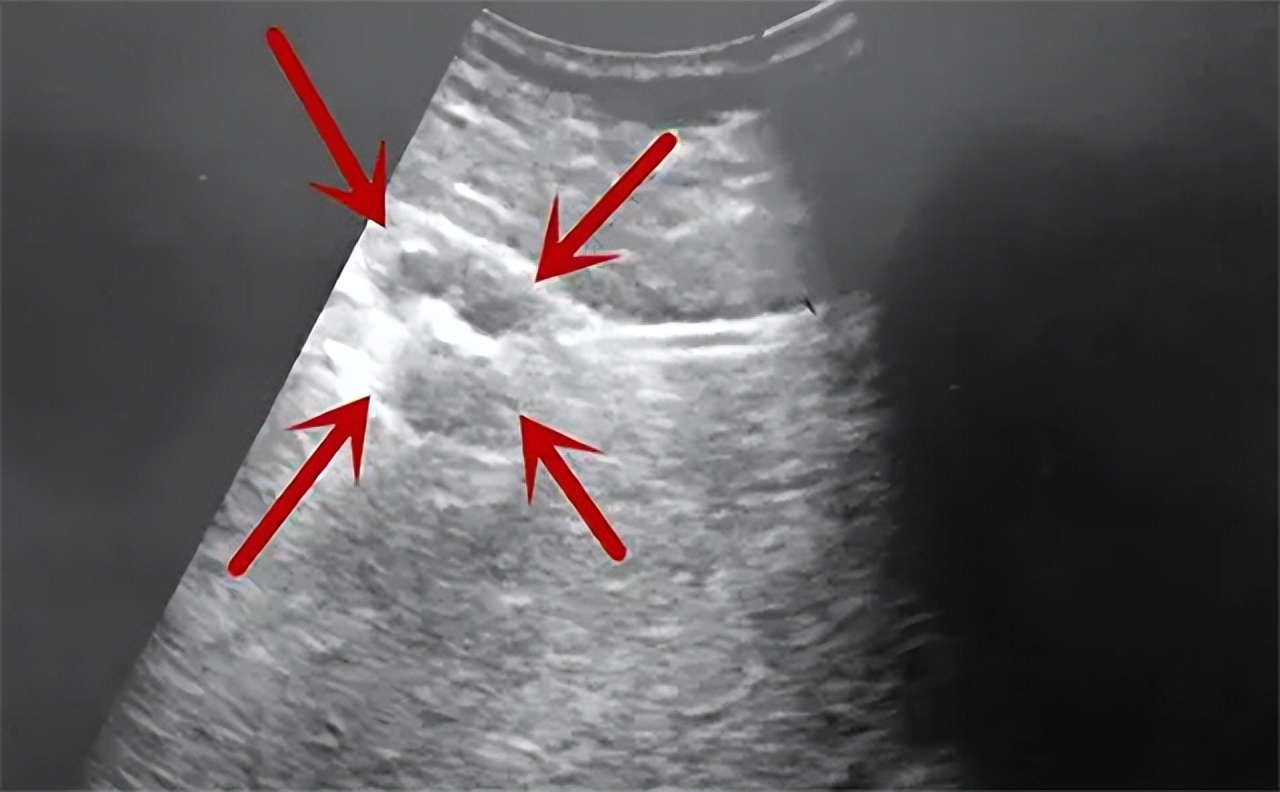

梁怡的肝脏部位有一个鸡蛋大小的瘤子,医生在看到检查结果的时候马上让梁怡又做了癌细胞ctDNA指标筛查和CT断层扫描。检查结果梁怡确诊肝癌晚期,肿瘤直径为10公分,同时发生了门静脉转移及肝内转移,按照标准已经属于肝癌晚期了。

在经过了整整14个月的联合治疗之后,梁怡再次做腹内彩超时已经能够看到肿瘤明显变小。原本10公分左右的肿瘤,此时已经只剩下3公分的大小。

梁怡的病情已经得到了控制。医生告诉梁怡,其发病的右半肝区已经发生了萎缩,而左边正常肝区由于代替右边肝脏发挥功能出现了增大的现象。因此判断右边肝区的肿瘤已经被药物“杀灭”。

尽管核磁共振及腹部彩超的评估中张万广教授和几位专家一致认为梁怡肝脏上的肿瘤已经失活,但是在血液肿瘤特征基因检测中却依旧显示的是呈阳性。于是张万广教授建议对梁怡的肿瘤进行手术切除,确保病灶部位不再发生变化。